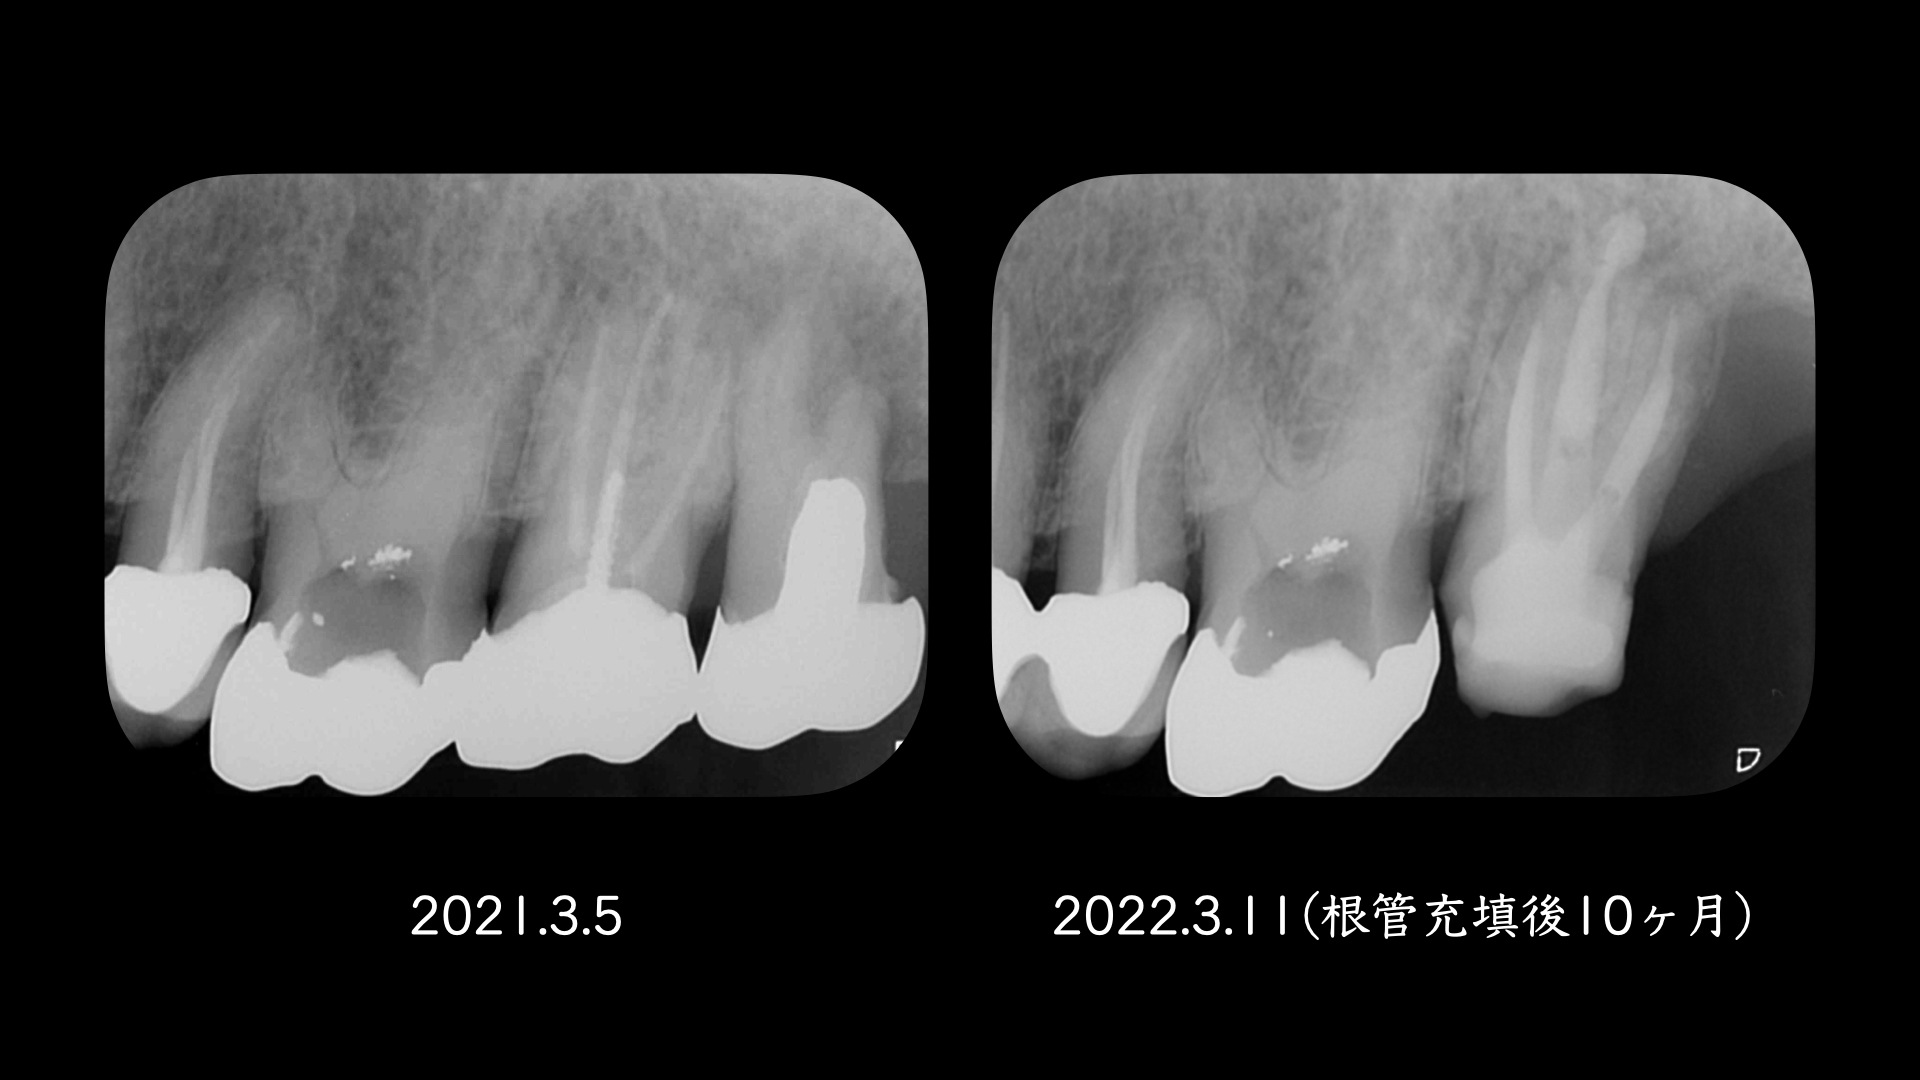

主訴時は症状がなかったので、経過をみていましたが、変化がないので治療することになりました。

右の画像のCT上で根尖部にかなり大きな透過像があります。

根管治療はマイクロスコープを使用し、根管内は綺麗になった。と判断したので2回でMTAセメントにより根管充填をおこないました。

噛み合わせの反対側(下顎)はインプラント治療をおこなっており、経過をみていましたが全く変化がありませんでした。